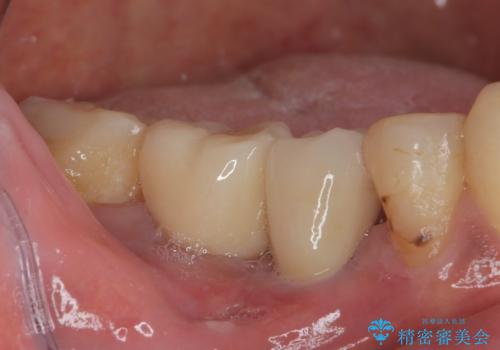

歯が割れて抜歯になってしまったとのことと、ブリッジの土台となる手前の歯は既に神経が取り除かれていて、こちらも破折するリスクが高いことから、咬合力に抵抗できるよう、インプラントによる補綴治療を行うこととしました。

手前の神経を取り除いている歯も、合わせて補綴治療を行うこととしました。

インプラント埋入時に植立具合の安定性を測定したところ、十分な数値が得られたため、速やかに仮歯を装着して咬合回復をさせることができました。

外科処置を1回に抑えることができ、あっという間に治療を終えることができました。